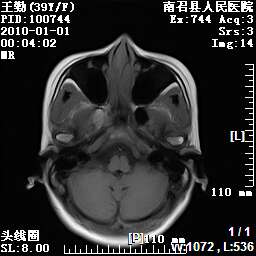

以下是引用随光逐影在2010-1-22 9:03:00的发言:[br]考虑左侧中颅窝(蝶骨翼区)脑膜瘤侵犯蝶骨翼并突入左侧眼眶。

以下是引用水过无痕在2010-1-22 14:55:00的发言:[br]一、定位:颅外占位;二、定性:恶性可能性大;三、组织来源:来源于左侧眼外直肌或其他部位;考虑为:横纹肌肉瘤>转移瘤>脑膜瘤.